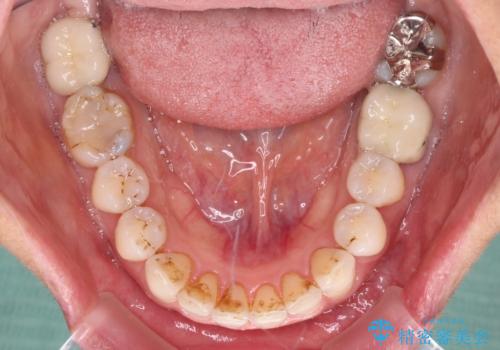

- 以前行った抜歯矯正が後戻りし、開いてしまったスペースが気になるとのことで来院された患者様です。

インビザラインを用いて開いてしまったスペースと前歯のデコボコを改善することとしました。

矯正治療後には気になっていた銀歯をセラミッククラウンやセラミックインレーにて治療することとしました。

上顎前歯を左右対称となるように歯列を整えたいとのことでしたが、すり減って形態が大きく異なっていたため、できる範囲での仕上がりとなりました。